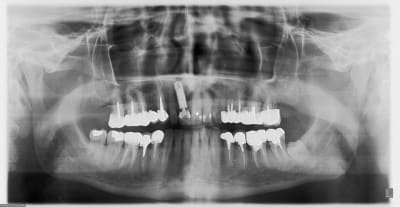

bon, c'est fait...extrac/implantation immédiate/ prov immédiate...merci pour vos tutos...;-)) çà m'a bien aidé...

implant Zimmer 4.7/16, membrane vestibulaire Zimmer socket repair, comblement au biooss...

pilier qui traverse la membrane...

juste surpris que le pilier prov en plastique soit pas radio-opaque...

j'ai volontairement un peu angulé vers la 12 car le canal palatin étais volumineux (vu au scan) et je voulais pas taper dedans...(maintenant la déformation géométrique de la pano amplifie un peu le phénomène...)

Merci...là c'est sûr...je suis ras les fosses nasales...

La stab primaire était très bonne et peu de perte de corticale vestibulaire (7/8mm en V et pas très large)...voilà pourquoi j'ai osé...le plus long...ajuster la prov...en fait j'avais peur au niveau de la vis...mais en fait il y a un hexagone sur pratiquement toute la longueur...

Pour la taille de l'implant...je me suis dit...va jusqu'où tu peux...et tu verras...;-))